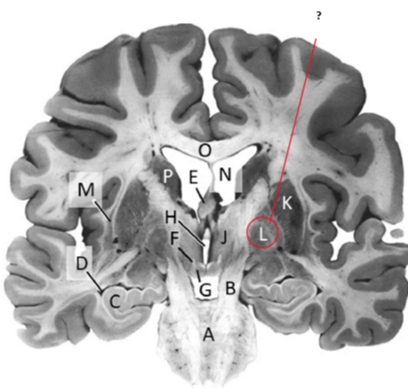

Name this and state its function.

Hippocampus.

Claustrum.

Name.

Temporal horn of lateral ventricle.